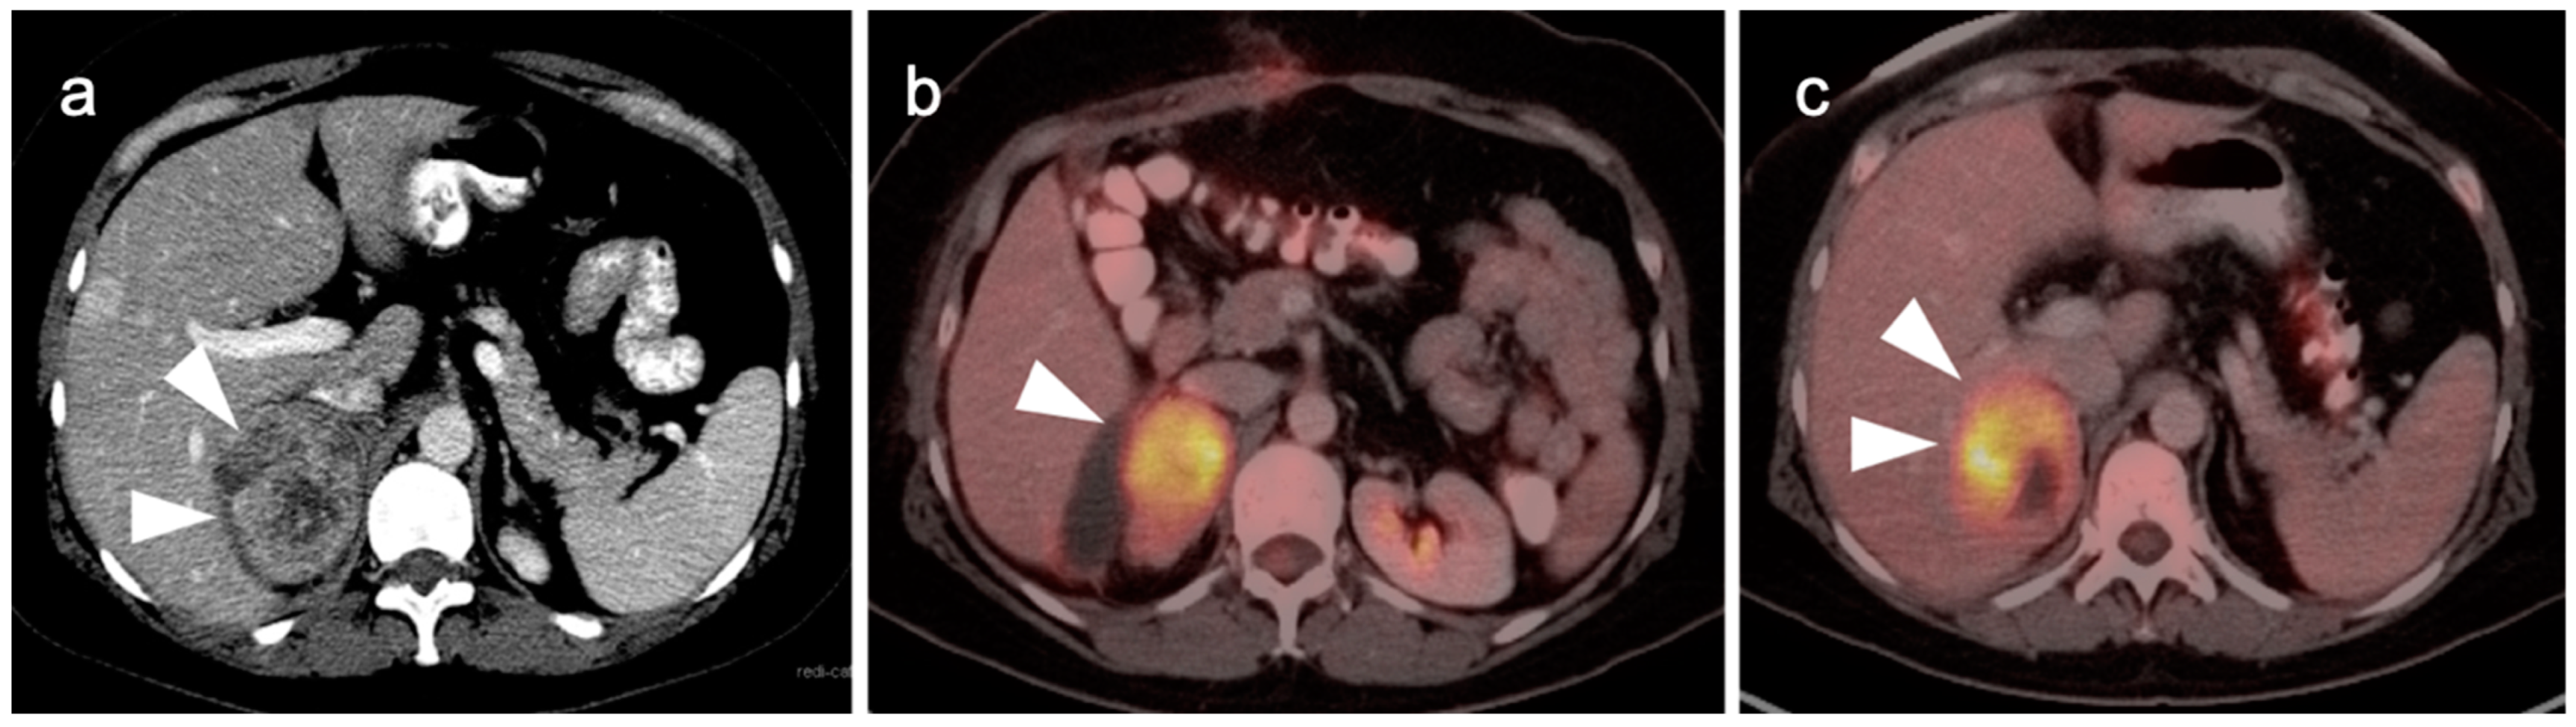

4. Hepatocellular Carcinoma